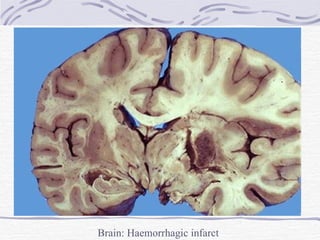

Ischaemic Stroke Infarction (stroke) Thrombotic – usually  anaemic  (may be haemorrhagic) Embolic – usually  haemorrhagic , often  multiple.  Haemorrhagic nature due to: Necrosis of vessel wall Lysis of embolus with restoration of some blood flow.

CNS Infarction Vascular occlusion causes: Necrosis of neurons, neuroglia and blood vessels 4-6 hrs. – coagulative necrosis 12-15 hrs. – sharp demarcation (swelling of neuropil) 24 hrs. – reactive changes Proliferation of microglia, astrocytes, capillaries Inflammatory reaction

CNS Infarction Infarction contd. 1-2 weeks – Swelling resolves Softening Shrunken granular grey matter Accumulation of lipid-laden phagocytes (gitter cells) in infarcted area Several months – shrunken cystic lesion traversed by glial fibrils and small blood vessels

Brain: Haemorrhagic infarct